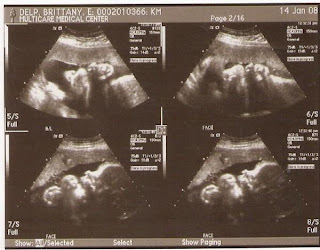

Ultrasound pictures!

These are amazing! 35 week ultrasounds taken today :)

Ear and face

Profile

Sucking her hand seems to be her favorite activity!

Check out the top left picture, that's her nose and lips!